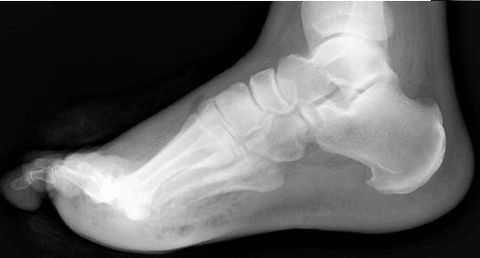

What foot type does this calcaneal inclination angle indicate? | Pes plano-valgus |

What is this angle called? What foot type does it indicate? | Talar - 1st MT or Meary's Angle Pes plano-valgus |